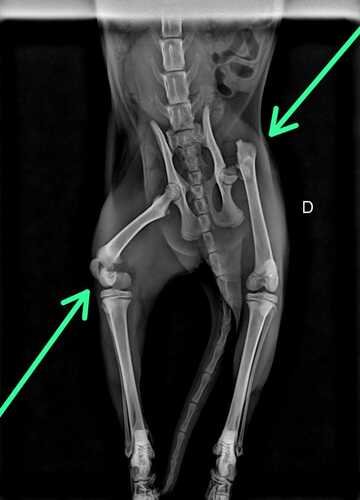

Venho por meio desta vaquinha, pedir a sua ajuda. A Meg, uma gatinha frágil de 5 meses, sofreu um acidente. Não sabemos ao certo se foi por maldade humana ou por algum acidente envolvendo um veículo de porte pequeno. Esse acidente ocasionou na fratura da cabeça do seu fêmur, e do fêmur.

O valor pedido será para custear as duas cirurgias, de ambos os lados, a diária da clínica e os medicamentos.